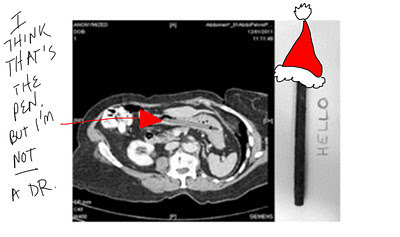

25 years ago a woman was standing on a set of stairs using a felt tipped pen to poke at something in her throat. Something else happened and she swallowed the pen. (She said she was standing on a set of stairs using a felt tip pen and a mirror to poke at a lump in her throat, I do not know. I suspect she does not know. In fact, I suspect if the pen hadn't caused her problems in the future it would have been an insignificant side note in the family history.) She told the doctor and her husband but they didn't believe her. (This story sounds taller and taller to me. I wouldn't have believed it. "Excuse me, Irene, you were doing what with what while on the what? Oh, please.") Fast forward to today when she had the pen removed and the pen was still capable of writing. (Note to manufacturer: Your pen obviously has staying power. You might want to buy it and put it in your museum of weirdness. Or maybe make a commercial with Charley Sheen. Either would work well.)

I see the pen. Also I see massive depression and two dogs playing ping pongwhile playing pinochle. (I was just playing with some Rorschachs's cards. If

you don't get this reference, it's because you didn't take Psych 101 in college

or you didn't watch One Flew Over the Cuckoo's Nest.)Oh, wait. I forgot this is a Christmas themed blog. I must go back and illustrate in my twisted manner.

Do you think the woman gave her permission for herx-rays to be posted ALL over the Internet? Because

if it was me who had a 25 year old pen lodged

inside me because I was obviously completely

effed up, standing on some stairs poking a pen

down my throat to see something about

my tonsils, I WOULD NOT give permission

to share with the entire freakin' world.What does this have to do with Christmas? Not a lot, but the story amused me and I did initially bring up the possibility of things shooting out of people's noses. (Wouldn't it have been funny if this woman had sneezed at the holiday dinner table and a 25 year old felt tip pen came shooting out of her nose? Well, probably not.)